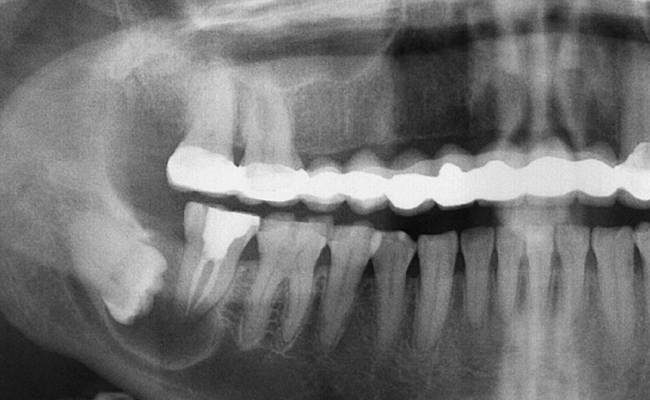

Radiography

Also Known as X-RAY. An X-ray is a quick, painless test that produces images of the structures inside your body, particularly your bones. It is used in diagnosis of caries, infection in periapical region, tooth position within the jaw.